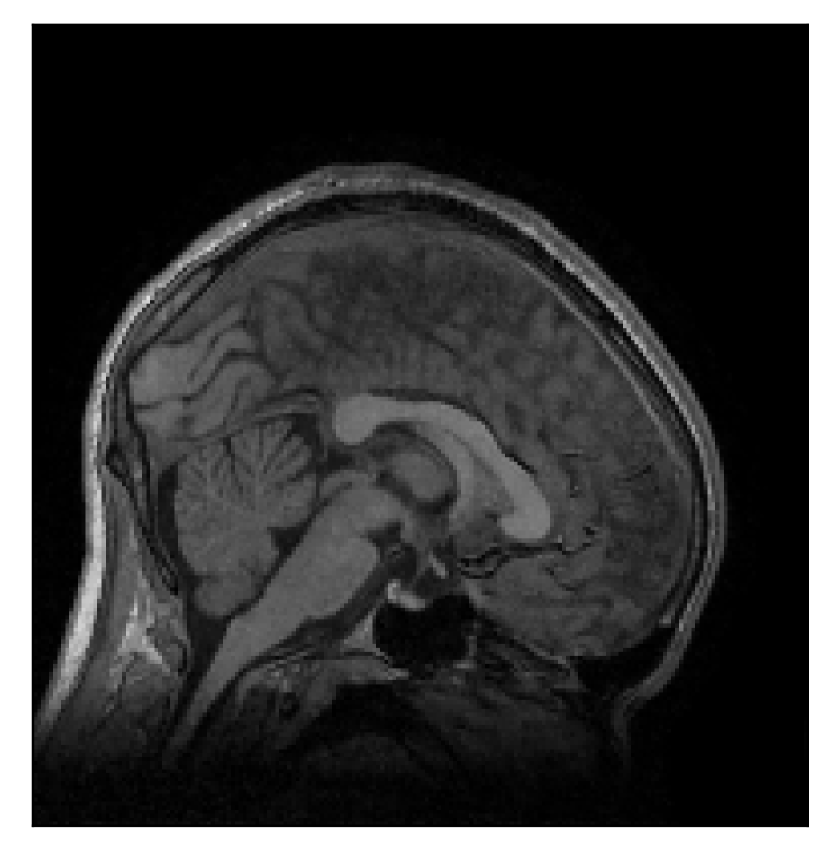

The second experiment is set up similarly to the previous one. We asked volunteer 3 to change position only once during the acquisition phase. We consider, now, a corrupted T2-FLAIR-weighted contrast with a reference T1-weighted contrast (see Table 1). The most important difference with the previous experiment, besides the type of contrast pair considered, is related to the randomized acquisition protocol. In this case, the scanner reconstruction employs a compressed-sensing reconstruction, and is not suited as input for the proposed motion-correction algorithm (see Appendix A). Therefore, for adequate motion correction, we must set up an intermediate step for processing the raw -space data via the SENSE reconstruction.

We further discuss the results of this experiment in Section 4.3.

| Section 3.3, Figure 14 | Sagittal | 24.72 | 28.76 | 0.6762 | 0.7818 |

| Coronal | 25.95 | 29.54 | 0.7238 | 0.8107 | |

| Axial | 25.08 | 29.59 | 0.7263 | 0.8407 | |

The motion-corrected full-volume scans were analyzed by a neuroradiologist with 16 years of experience. These were generally deemed of good radiological quality. The motion-related artifacts have been completely removed, and the results are quite close to the ground truth. In Table 3, we organized a more detailed qualitative analysis of the 3D results, geared toward a radiological assessment of the corrected scans.

| Section 3.3, Figure 14 | T2-FLAIR | Completely corrected | Some blurring | No additional artifacts | Good grey white matter differentiation |

4.3 Experiment 3: scanner reconstruction vs raw k-space data

The results of the two experiments described in Section 3.3 are depicted in Figures 12 and 14. The main difference between the two experiments is related to the input data for the proposed motion-correction algorithm.

In the case of randomized sampling, the scanner reconstruction is not adequate as input data for the proposed motion-correction algorithm, because it employs a compressed-sensing algorithm. We speculate that compressed-sensing reconstructions degrade the information contained in the corrupted volume, and the corrected contrast cannot be effectively recovered by simply removing rigid-motion artifacts (we defer the degraded results when using scanner reconstruction data in Appendix A). However, when the input data is obtained by directly processing the raw -space data via the SENSE reconstruction, the motion-correction scheme is able to successfully remove the motion artifacts (Figure 14).